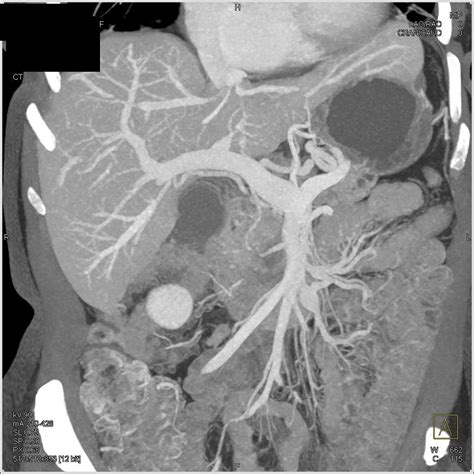

To understand dilation, one must first understand the anatomy. The main pancreatic duct, or the Duct of Wirsung, typically runs the length of the pancreas. In a healthy individual, this duct has a specific, narrow diameter. When a radiologist performs an ultrasound, CT scan, or MRI and notes an enlarged pancreatic duct, they are observing that the diameter of this duct exceeds the normal, expected measurement. This dilation is rarely a condition in itself; rather, it is usually a symptom or a sign of an underlying issue causing back-pressure or blockage within the ductal system.

CT Scan with Contrast Provides detailed cross-sectional images to look for masses, inflammation, or large stones.